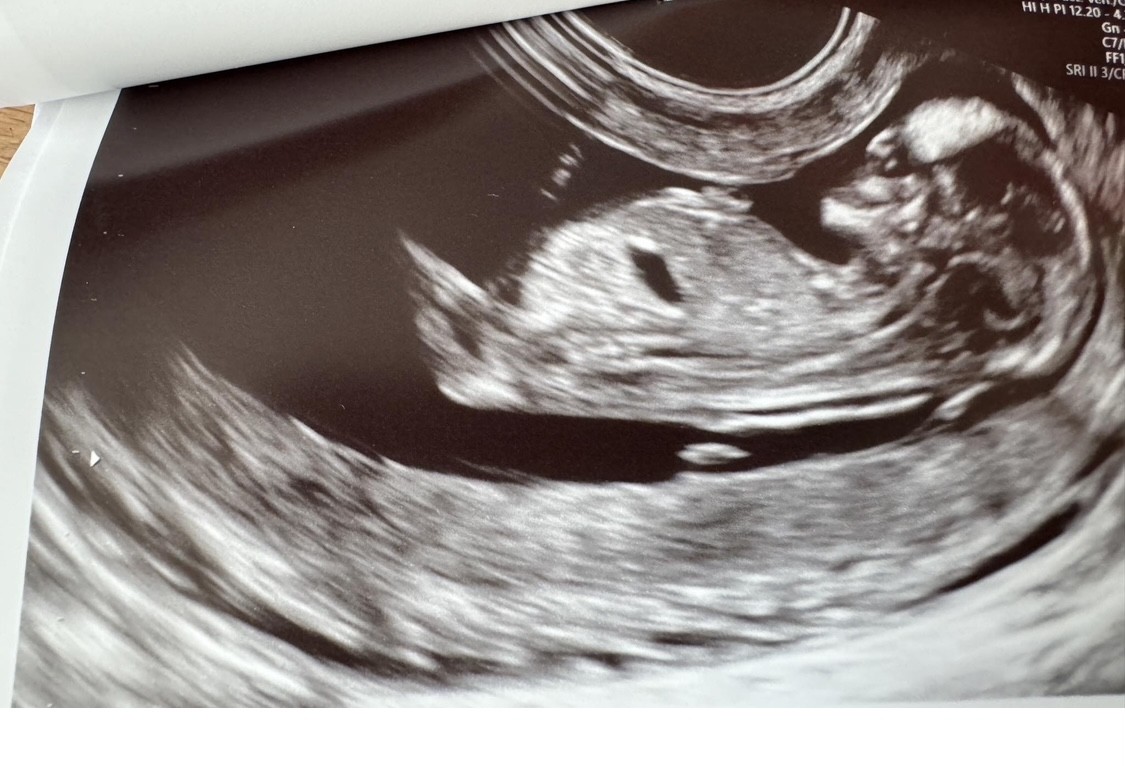

Zaczynam właśnie 7 miesiąc ciazy, czas kompletować wyprawkę :) na 1 prenatalnych i wizytach lekarskich do 19 tyg chłopak, widziałam siusiaka, w 20 tyg na 70% dziewczynka, później już nic nie było widać… ostatnie USG, ułożenie miednicowe, pępowina między nogami :p czy na tych zdjęciach da się coś rozpoznać względem wyrostka? :)

• IMG_7106.jpeg

IMG_7106.jpeg

199,7 KB · Wyświetleń: 78